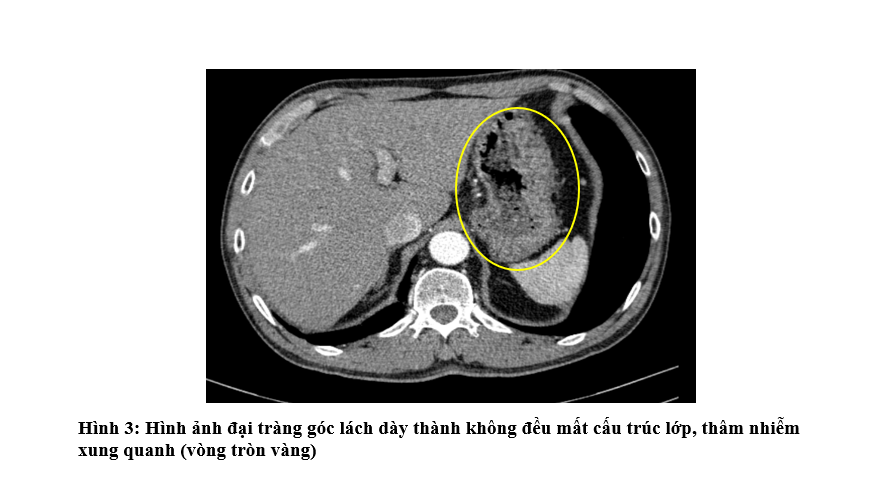

- Chụp Cắt lớp vi tính ổ bụng: Hình ảnh khối tuyến thượng thận trái 21x32mm - theo dõi tổn thương thứ phát. Đại tràng góc lách dày thành không đều quanh chu vi 15mm trên đoạn dài 61mm mất cấu trúc lớp, thâm nhiễm xung quanh kèm nhiều hạch lân cận lớn nhất kích thước 9x5mm

- Chụp PET/CT: Hình ảnh dày thành đại tràng góc lách, dày nhất 18mm, trên đoạn 41mm, tăng chuyển hóa, thâm nhiễm mỡ xung quanh. Vài hạch ở cạnh tổn thương đại tràng, cạnh động mạch chủ bụng và cạnh thân tụy tăng chuyển hóa, khả năng do di căn. Hình ảnh tổn thương bờ tua gai ở S3 phổi trái, kích thước 31x26x22mm, tăng chuyển hóa, khả năng là tổn thương ác tính nguyên phát. Hình ảnh vài hạch trung thất nhóm 5, 6, 7, hạch thượng đòn Phải tăng chuyển hóa, khả năng do di căn. Hình ảnh vài nốt bán đặc và kính mờ rải rác nhu mô phổi 2 bên, có nốt tăng chuyển hóa, khả năng do di căn